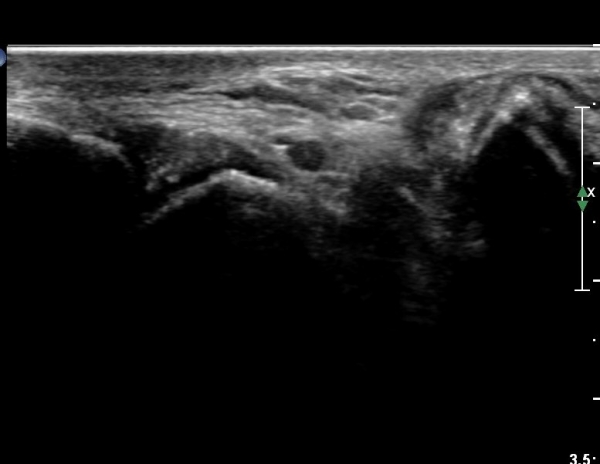

Àü°ÅºñÀδë Á¾´Ü¸é°Ë»ç¿¡¼­ Àü°Åºñ ÀδëÀÇ Àú¿¡ÄÚ ºÎÁ¶À» º¸ÀÓ(»çÁø 2).